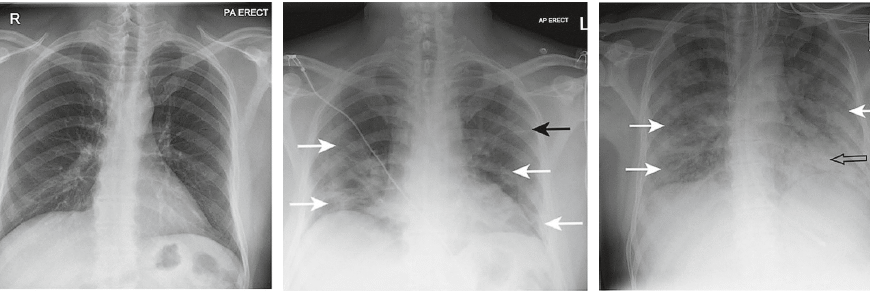

- Рентгенографія грудної клітки: щоб побачити те, чого не видно неозброєним оком.